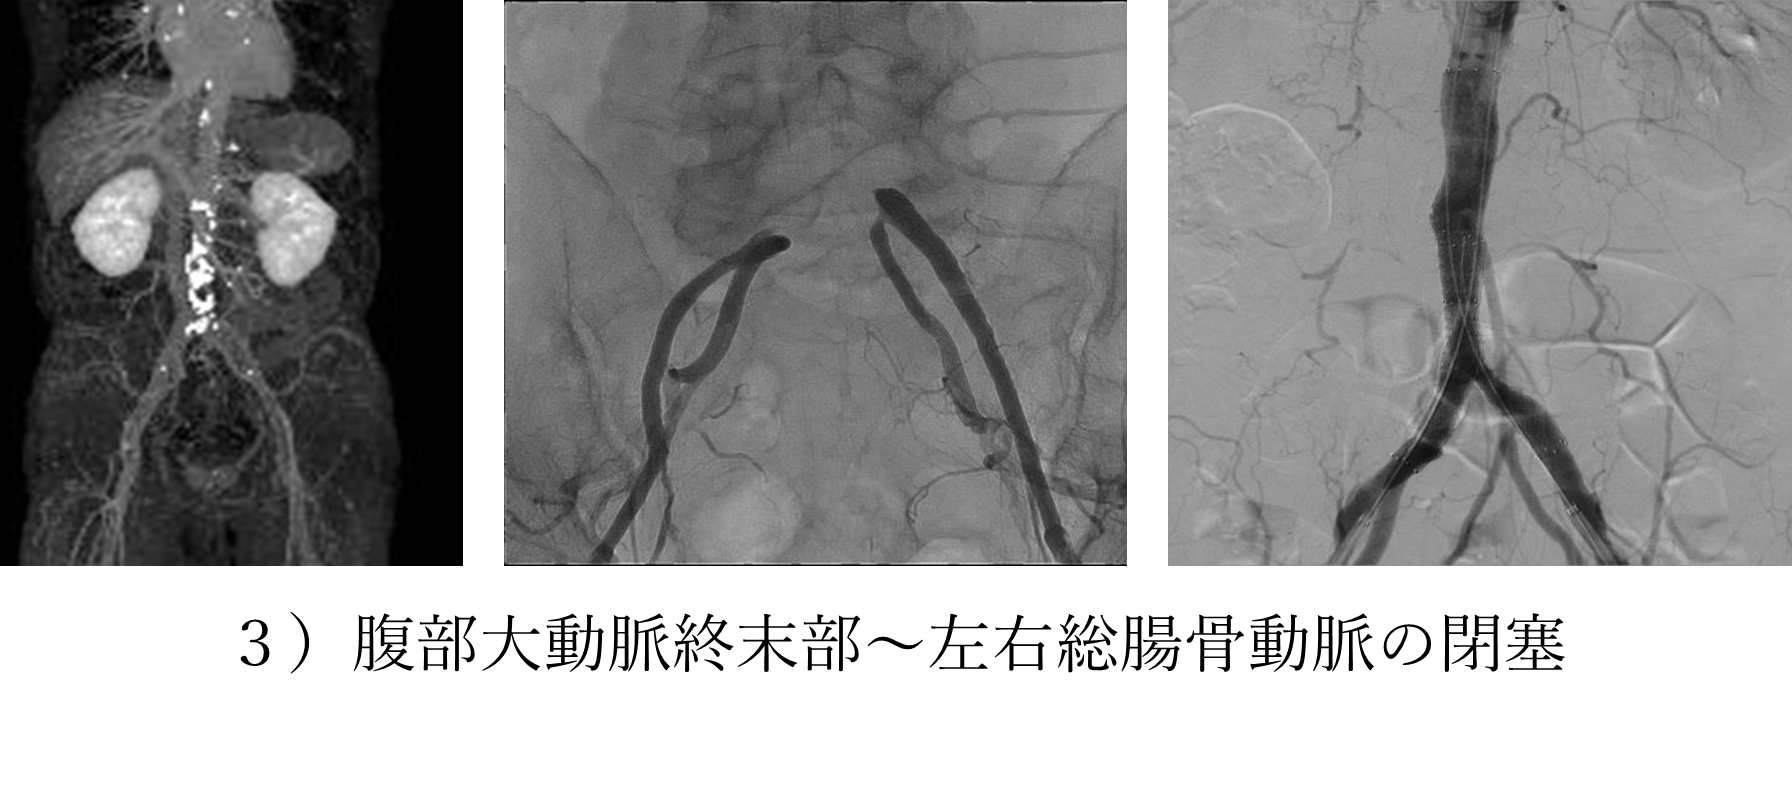

下にいくつかの症例を提示いたしますが、末梢動脈疾患も例えば1)の左鎖骨下動脈狭窄症の方はシャンプーをするときに左腕がだるくて洗い続けることができず、血圧の左右差を認めているということで御紹介いただいた方の治療前後の画像となります。

そのほか、3)のように腹部大動脈終末部の閉塞に対してのカテーテル治療なども今はカテーテル治療の成績が良くなっております。